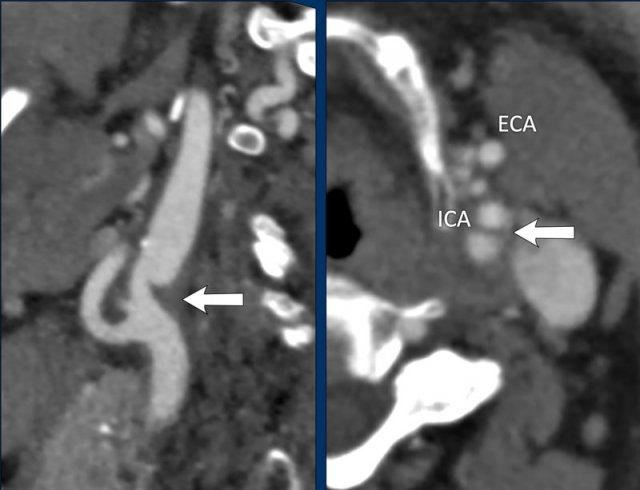

Tắc Nghẽn Giả

Tắc nghẽn giả động mạch cảnh trong đoạn cổ là tình trạng tắc nghẽn đơn độc của động mạch cảnh trong (ICA) đoạn nội sọ xa, bắt chước hình ảnh tắc nghẽn ICA ngoài sọ trên CTA hoặc DSA.

Trong tắc nghẽn giả, hình ảnh trông như thể có tắc hoàn toàn tại ICA ngay trên mức xoang cảnh.

Thuốc cản quang đi vào ICA gặp khó khăn khi di chuyển lên phía trên do máu ứ đọng trong lòng ICA, vì ICA không có các nhánh bên lớn.

Thuốc cản quang chỉ thấm chậm vào cột máu ứ đọng này, tạo ra hình ảnh loang màu nước.

Trên CTA, có thể thấy tỷ trọng thuốc cản quang giảm dần trong ICA với hình ảnh loang màu nước.

Vấn đề cốt lõi là tắc nghẽn dòng chảy ra tại mức đỉnh chữ T động mạch cảnh.

Hai trường hợp tắc nghẽn giả động mạch cảnh.

Trong trường hợp đầu tiên (bên trái), thuốc cản quang dừng khá đột ngột, mặc dù có thể thấy một vùng nhỏ với tỷ trọng thuốc giảm dần.

Trong trường hợp này, việc phân biệt giữa tắc nghẽn giả với lóc tách thành mạch hoặc tắc nghẽn do xơ vữa có thể khó khăn.

Tuy nhiên, chúng ta không thấy hình dạng ngọn lửa điển hình của xoang cảnh như trong lóc tách thành mạch, và không có dấu hiệu xơ vữa động mạch (không có mảng xơ vữa hay vôi hóa).

Trong trường hợp thứ hai, tỷ trọng thuốc cản quang giảm dần rõ ràng trên một đoạn dài hơn (đầu mũi tên).

Đây rõ ràng là tắc nghẽn giả động mạch cảnh.